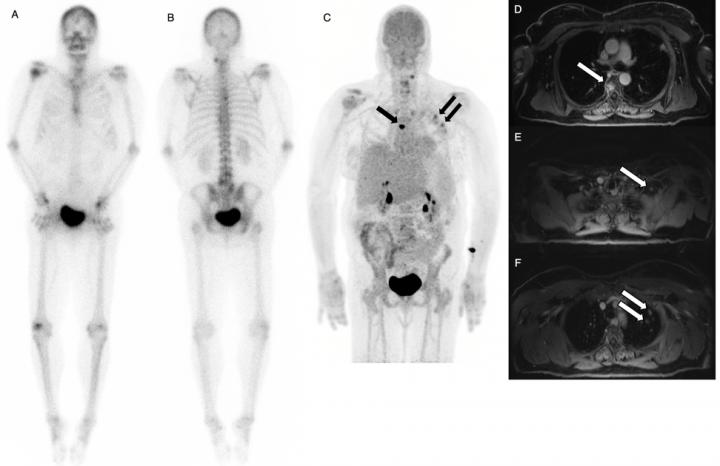

A 50 Year-Old Woman with Recurrent Breast Cancer

image: Tc-99m MDP bone scan (left) is negative for osseous lesions. NaF/FDG PET/MRI (right and second slide) confirms absence of bone metastases, but shows liver metastases. view more

After injection, scientists performed PET/ MRI scans with time of flight capability and compared the results with conventional technetium 99m-methyl diphosphonate (99mTc MDP) bone scintigraphy. Results of the study showed improved detection of prostate and breast cancer that had metastasized to bone. Dual-agent PET/MR pointed to bone metastases in 22 patients who were also found positive for metastases with conventional bone scan. In addition, PET/MR detected more bone metastases in 14 patients when compared to the conventional bone scan, which caught only one lesion that was not detected by PET/MR.